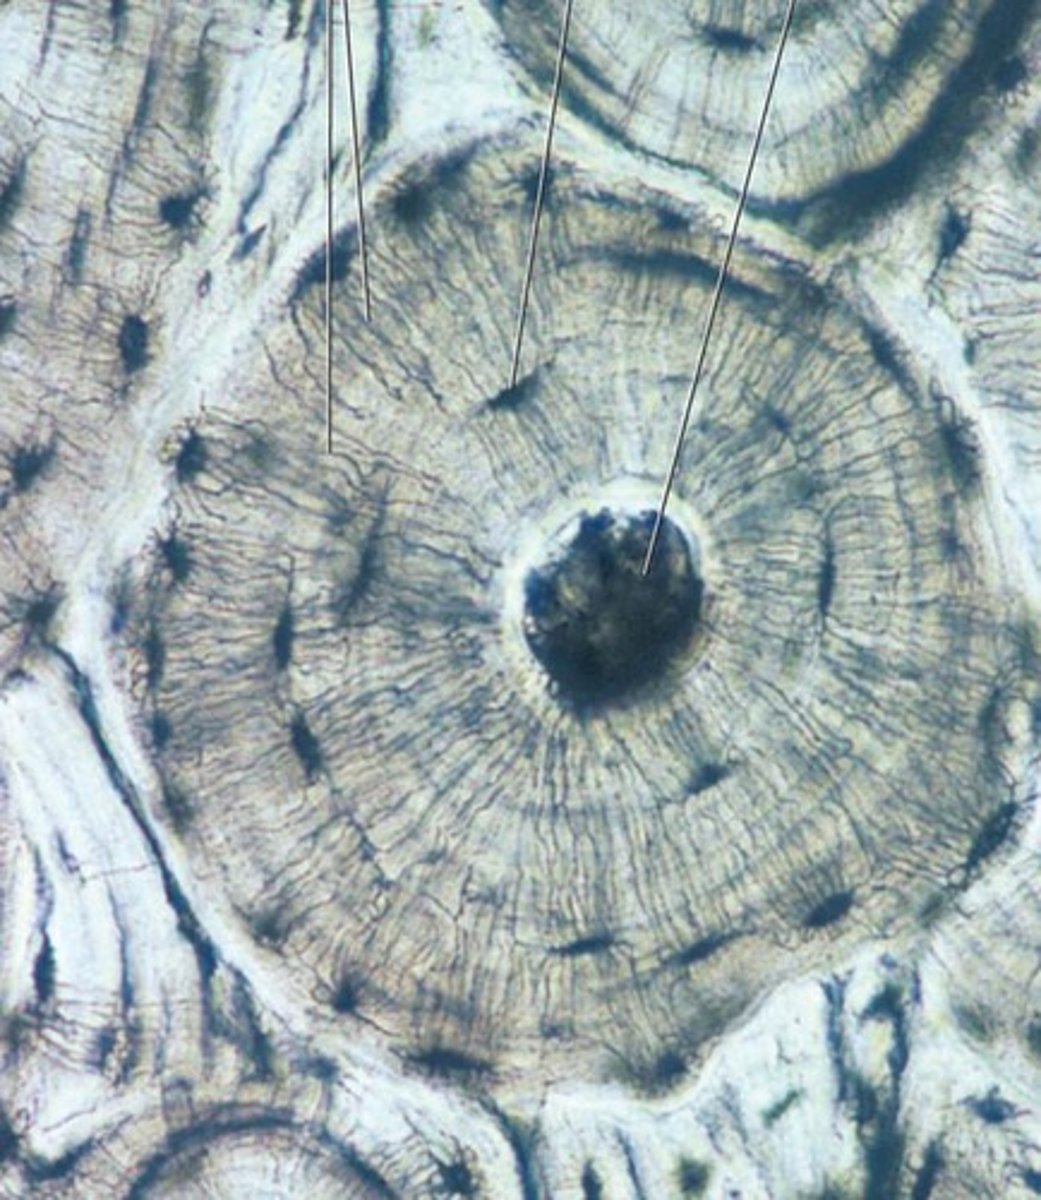

compact bone

dense, hard layers of bone tissue that lie underneath the periosteum

osteon

functional unit of compact bone

Canaliculi

little channels that connect lacunae

Haversian canal

Channels in bone that contain blood vessels and nerves

Osteocytes

mature bone cells

Lamellae

rings around the central canal, sites of lacunae